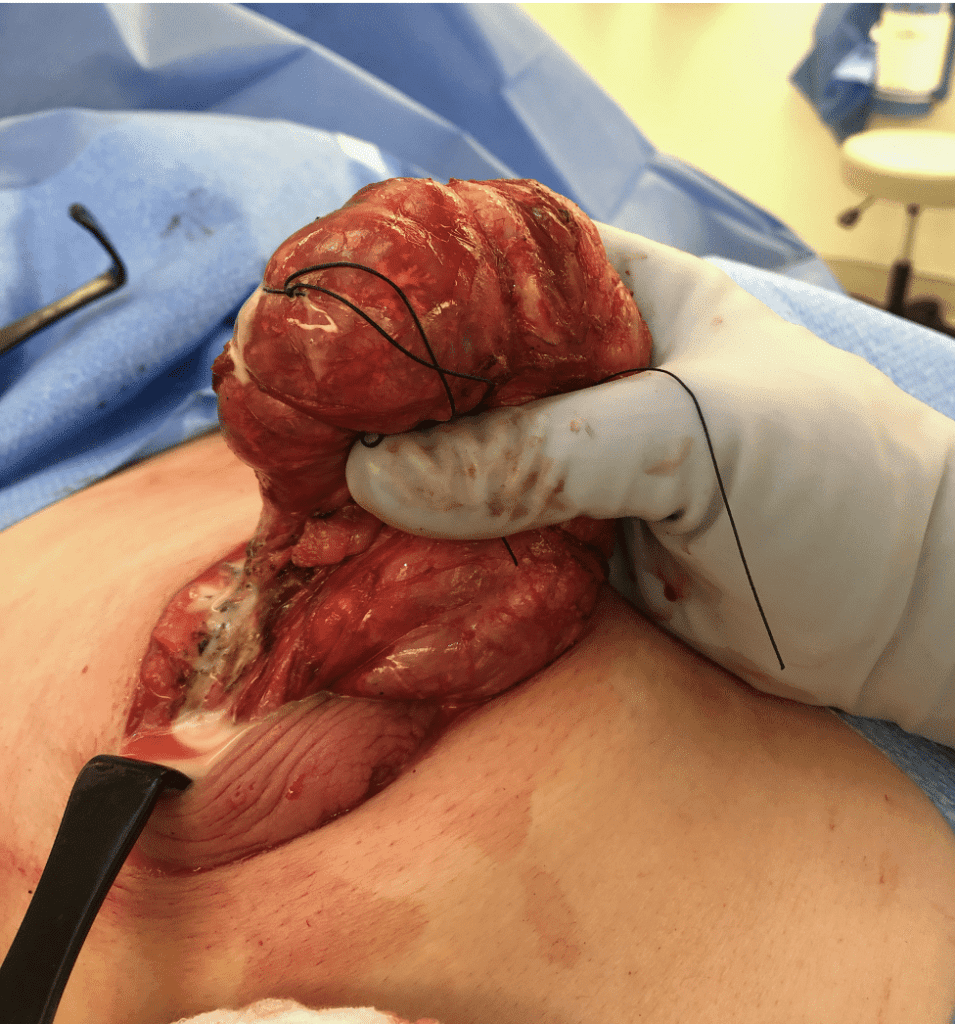

The video below demonstrates removal of a phyllodes lesion during lactation. There are several things to learn from this video:

- Breast imaging, breast biopsy, and breast surgery are safe during pregnancy and lactation. In fact, it would have been more ideal to remove this mass during pregnancy (before it grew and to rule out anything worrisome like a malignant phyllodes tumor). It also is far easier to operate without complication on a pregnant, rather than lactating, breast.

- In retrospect, this patient would have benefitted from a drain post-operatively rather than repeated aspirations.

- Breastmilk is under autocrine (local – i.e. the breasts function independently) control after two weeks postpartum (the first two weeks are endocrine, or central control). This means you can upregulate and downregulate the breasts independently.

- It is very important to treat hyperlactation (overproduction of breastmilk) in general, as well is when it is present when a patient requires surgery.